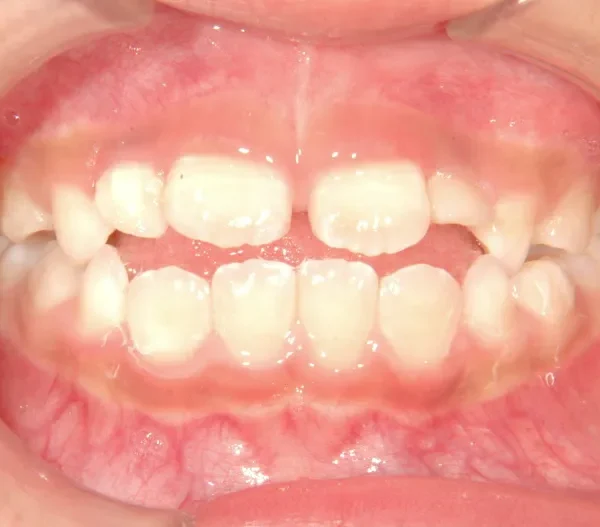

【子供の矯正(一期)】叢生・開咬・前歯で噛めない・舌癖・7歳女児【M.O様】

初診時年齢 小学校1年生 (女性) 主訴 前歯で噛めない

診断名 叢生・開咬 装置名

前歯で噛めない(開咬/オープンバイト)

舌の癖によって下の前歯が出て、上の前歯が短いです。

取り外し式の装置で上下の歯並びを拡げて、下の前歯を引っ込めます。

初診